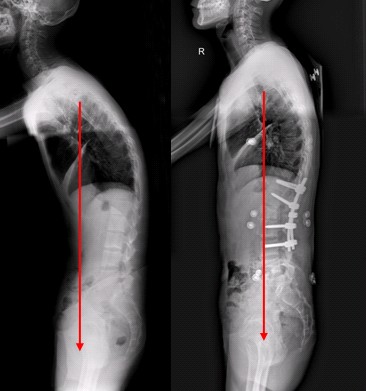

如今有太多的病折磨着病人,有的病甚至把病人折磨的生不如死,比如强直。这些病的严重程度足以引起大家的重视。很多健康的人士为了自己不受到这些病的侵犯,已经开始注意强直性脊柱炎了!那对于强直性脊柱炎患者要注意哪些呢?成都强直性脊柱炎治疗医生表示强调:强直性脊柱炎患者应坚持长期治疗!

医生表示:强直性脊柱炎病程缠绵,不少患者在治疗过程中存在急躁情绪,对坚持长期治疗缺乏足够的思想准备,情绪变得十分悲观,失去信心放弃治疗,这是很危险的。一定要克服急躁情绪,治疗及时恰当,树立起战胜疾病的信心。 >>>确诊后如何治疗?点击免费咨询在线医生

2、强直性脊柱炎患者应注意生理姿势

注意保持生理姿势,防止发生脊柱畸形和僵直。在休息时要保持适当的体位,应睡硬板床,取仰卧位,不垫枕头;在站立或坐位时,应尽量挺胸收腹;写字时桌子要高一些,椅子要矮 一些。凡能引起持续性疼痛的体力活动应该避免。